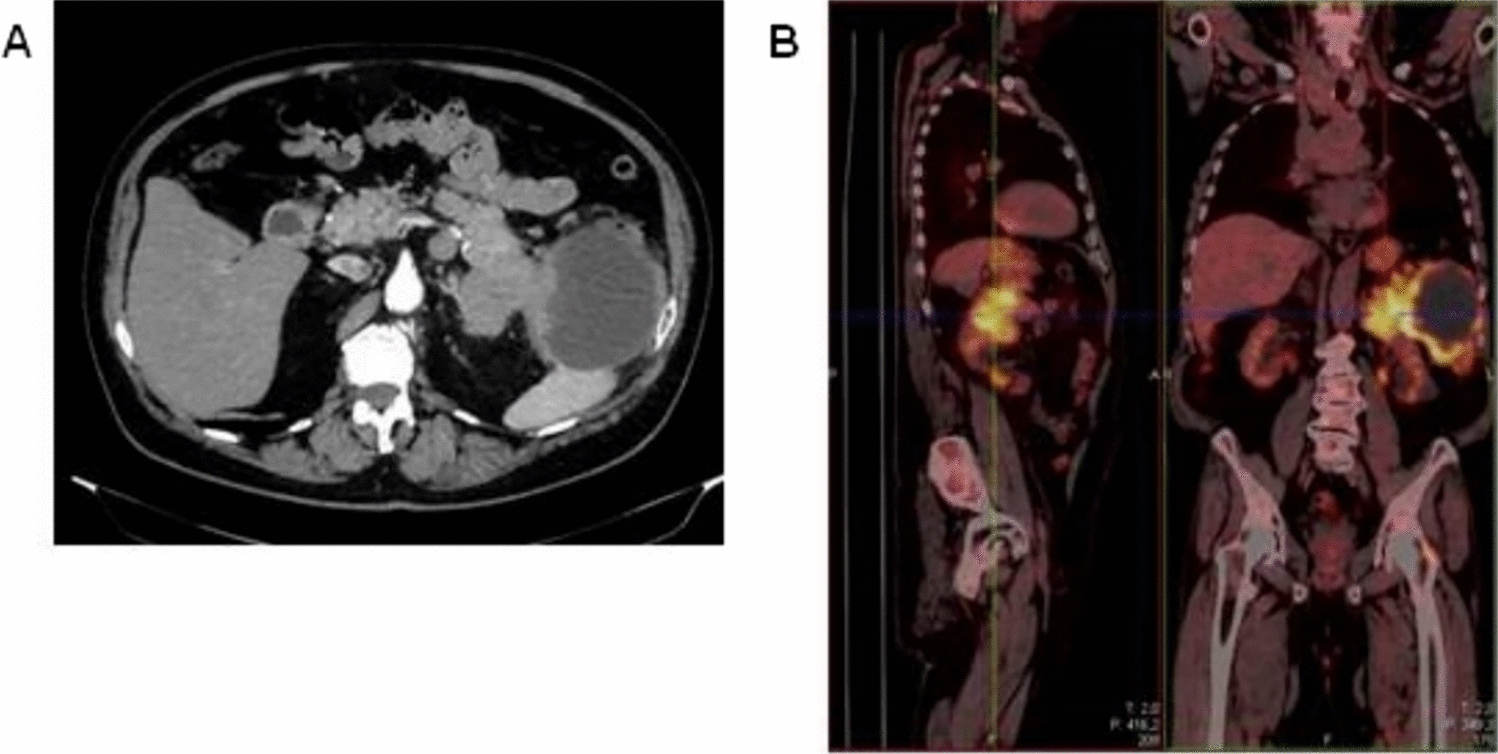

Computed tomography (CT) revealed confluent masses with a central hypodense component, occupying an area of 15 cm in the pancreatic tail. This lesion appeared not dissociable from the ascending colon, bordered the large gastric curvature, the left adrenal gland, the spleen and the abdominal wall (Fig. 1A). Gross locoregional lymphadenopathies were shown. Fluorodeoxyglucose (FDG)-positron emission tomography (PET) confirmed an extensive hypermetabolic infiltrating neoplastic mass, with locoregional lymph nodal metastases (Fig. 1B). The patient underwent endoscopic ultrasonography with fine-needle aspiration (EUS-FNA). The cytological examination revealed the diagnosis of pancreatic acinar adenocarcinoma, supported by immunohistochemical positivity for BCL-10 and negativity for chromogranin A and synaptophysin (Fig. 2A–D). CEA resulted over the upper limit, while CA-19.9 and AFP showed normal levels.

Fig. 1

CT (A) and PET (B) scans at baseline